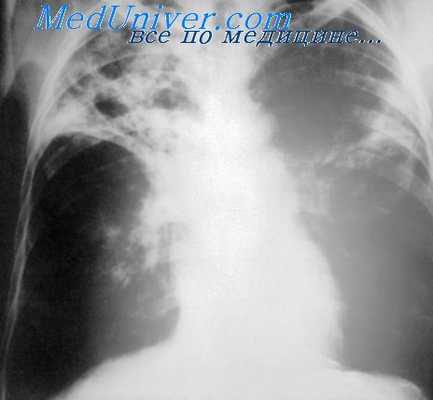

- Флюорография. Рентгеновские снимки выполняются в двух проекциях. Они показывают наличие новообразования, его размеры, локализацию, сдавление (стеноз) бронха.

- КТ. Компьютерная томография выполняется в трех проекциях. Это позволяет получить точную информацию о размерах опухоли, распространенности опухолевого процесса, вовлечении в него средостения, плевры, регионарных лимфоузлов, диафрагмы, оценить степень поражения бронхов (стеноза, окклюзии).

У абсолютного числа больных поражение в легком было распространенным, свидетельствующее о далеко зашедшем тяжелом процессе тотального повреждения одного легкого и у 93,5% изменение в другом (в том числе у 26 каверна в остающемся легком).

Таким образом, характер патологического процесса и его распространенность указывали на необратимость изменений, где нельзя было рассчитывать на излечение с помощью комплекса терапевтических мероприятий.